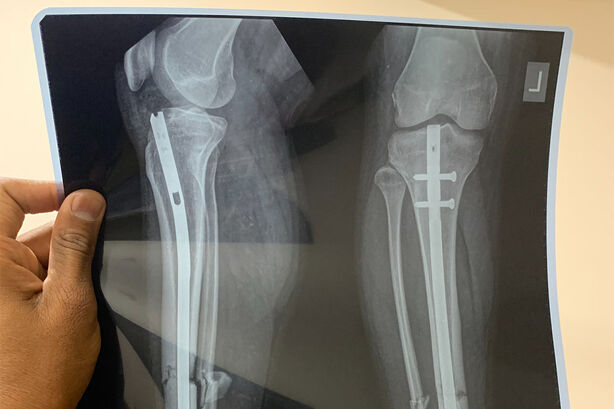

Umělá inteligence má lékařům v praxi pomoci zvládnout neustále se navyšující počet rentgenových snímků, které musí během roku vyhodnotit. Po rentgenovém vyšetření se snímky pomocí technologie české firmy OR-CZ uloží do počítače, kde je umělá inteligence Carebot vyhodnotí. Následně upozorní lékaře na problematická místa. Zabrání tak chybovosti při stanovování diagnózy.

Lékaři radiologického oddělení Nemocnice Havířov pomáhají ukončit fázi vývoje tohoto systému před tím, než bude moci být nasazen v nemocnicích i ordinacích po celé Evropě. Systém nyní zároveň prochází certifikací zdravotního prostředku.